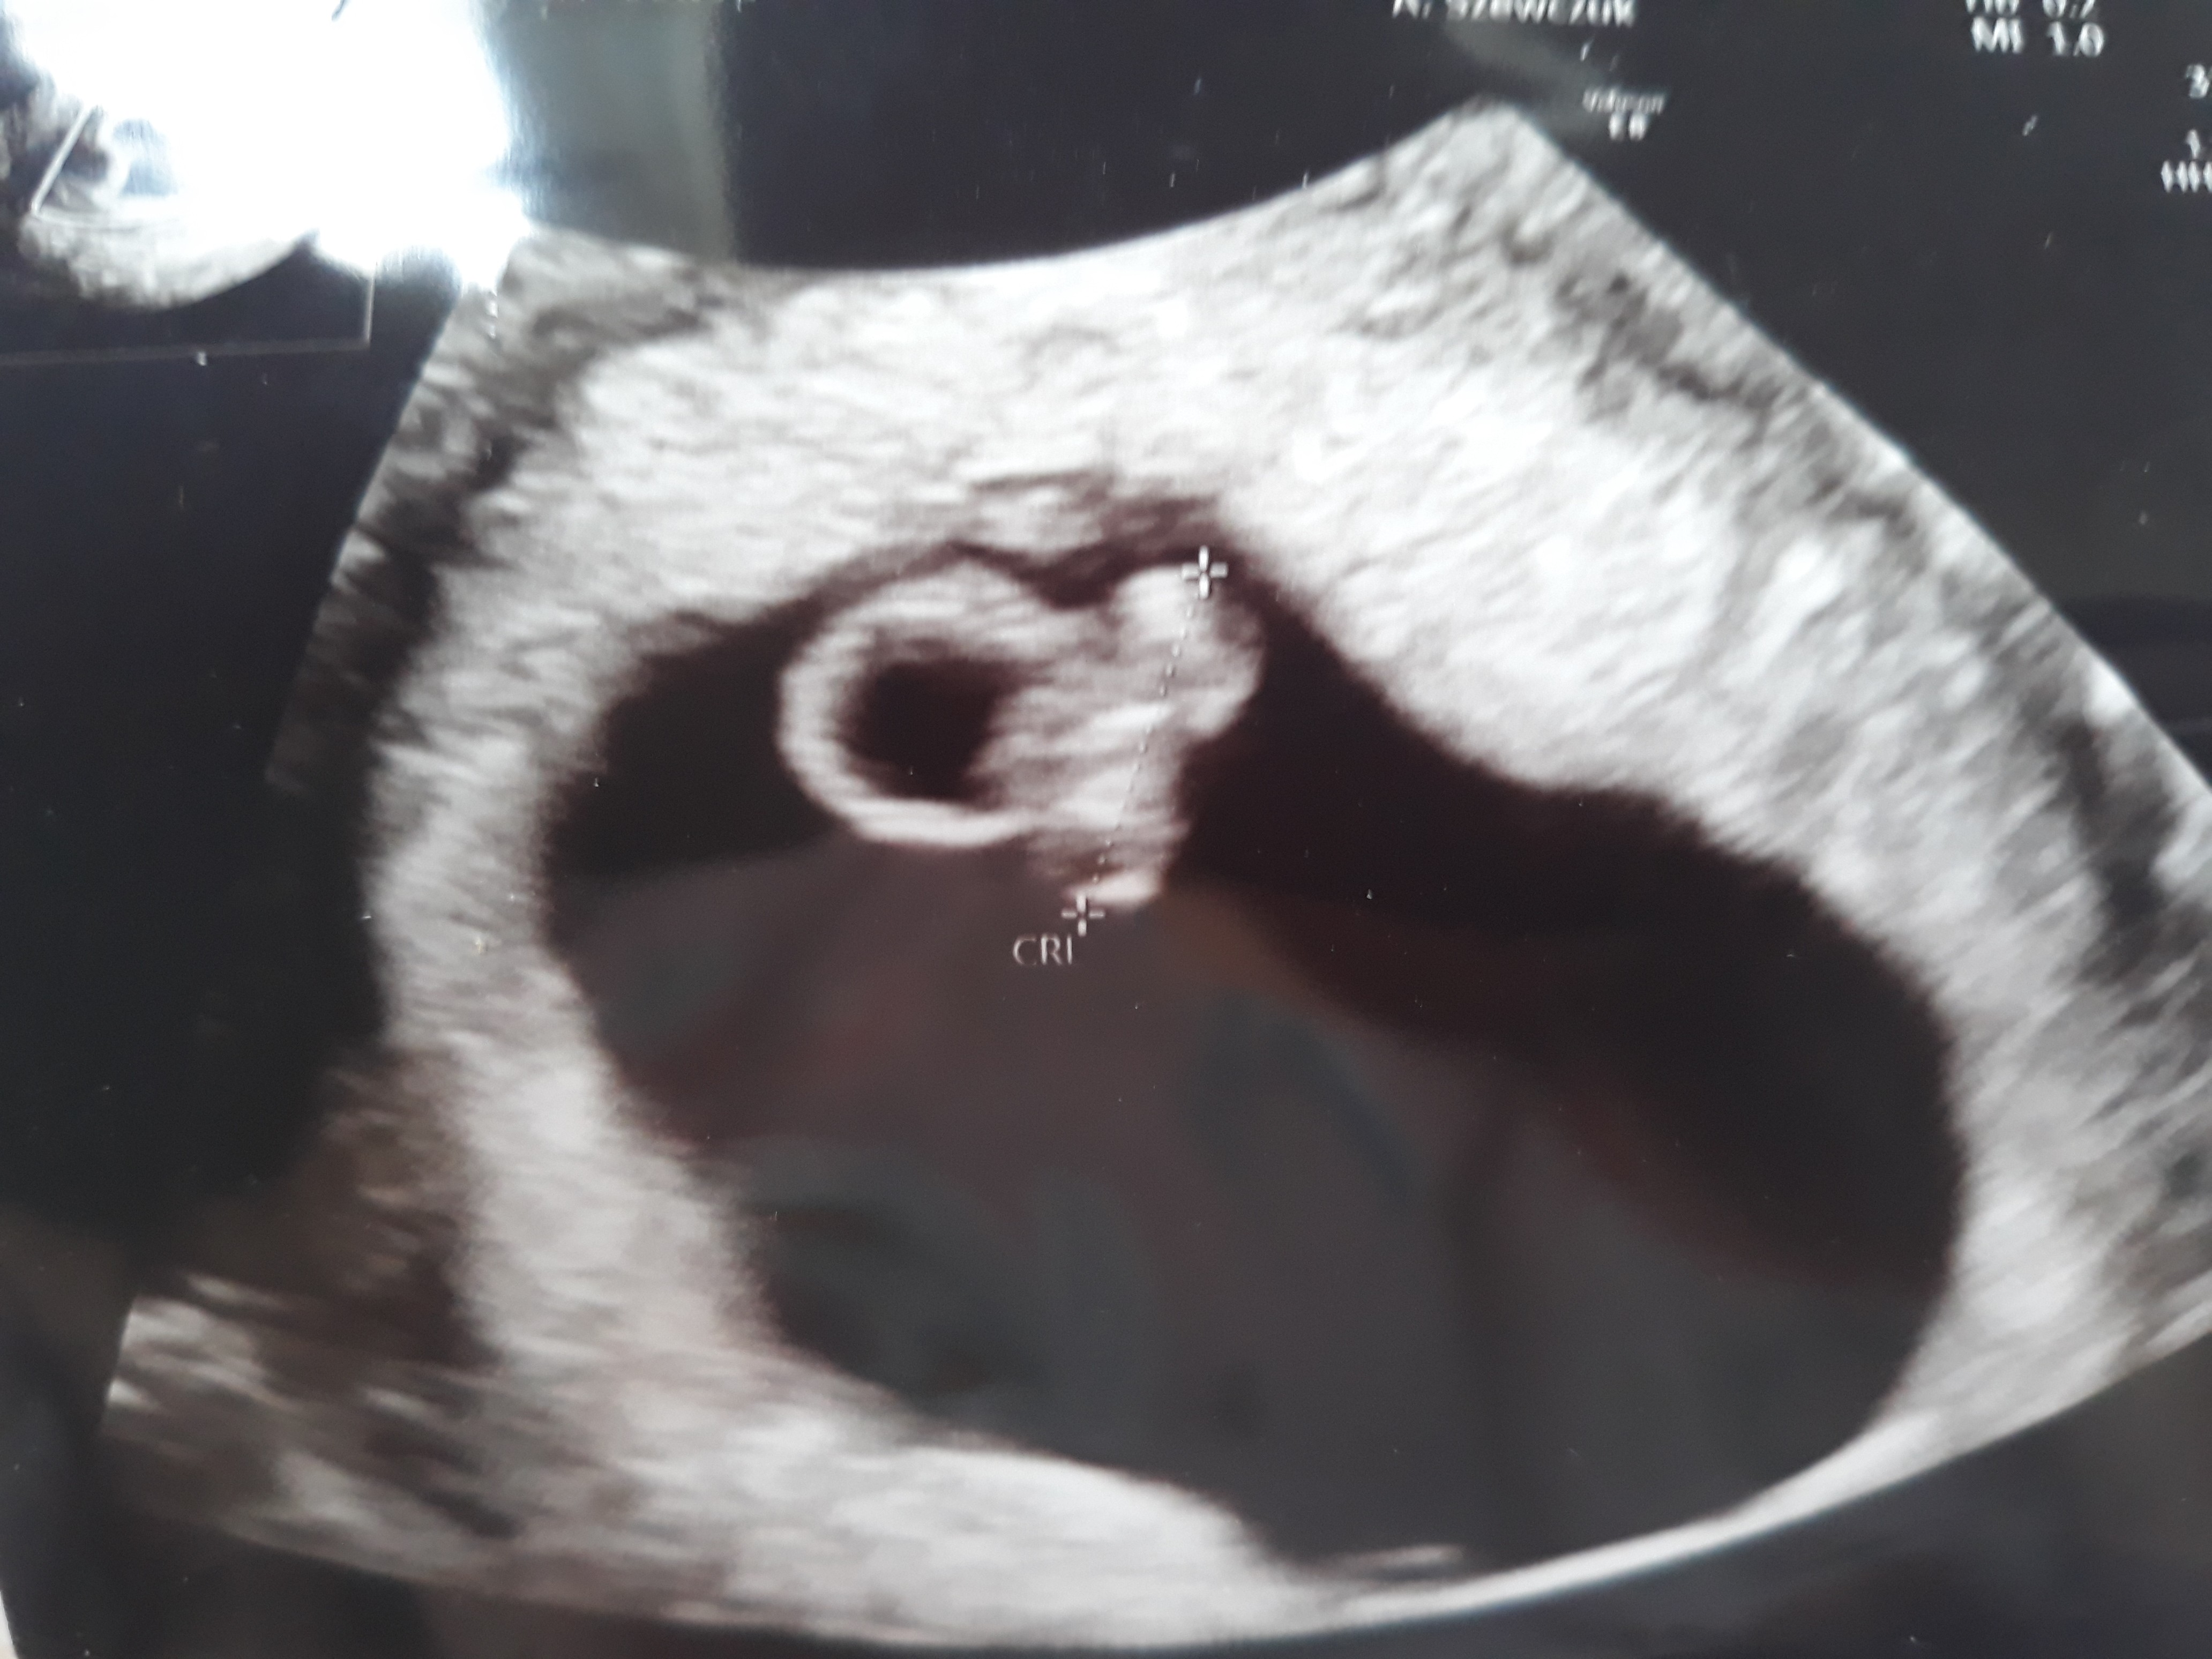

a jakiej wielkości zarodek?Patrzę teraz na to moje usg z 6+5 I się zastanawiam czy zarodek nie jest za malutki jak na tak duży pęcherzyk...

W tygodniu 6+5 miał 0,71 cma jakiej wielkości zarodek?

to moim zdaniem nie jest za mały u mnie przy 6w 0d nawet nie zmierzyła bo za tyciusieW tygodniu 6+5 miał 0,71 cm

Bardzo dobry rozmiarW tygodniu 6+5 miał 0,71 cm

Zarodek miał 0,71, ale zobaczcie w jakim jest dużym pęcherzyku.to moim zdaniem nie jest za mały u mnie przy 6w 0d nawet nie zmierzyła bo za tyciusie